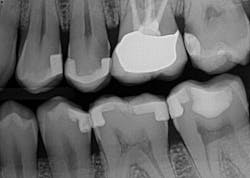

Figure 1: A patient presented for a new-patient examination. During the appointment, radiographic decay was noted on Nos. 12, 13, and 15. Treatment plan options were given to the patient. The patient elected to have Nos. 13 and 15 crowned and to have No. 12 restored with a new composite filling.

Figure 5: The radiographic results of the fillings, buildups, and bonded e.max restorations feature highly radiopaque bonding materials.